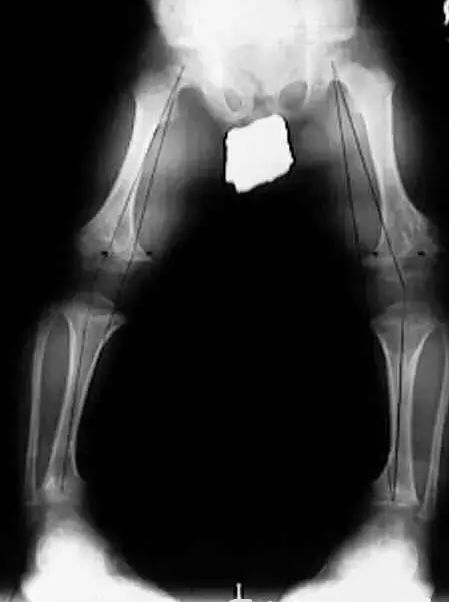

人在双下肢站立时,双足跟并拢,双膝关节若不能够靠在一起,存在距离,形成O形状,医学上称之为膝内翻畸形,俗称O型腿,又称罗圈腿。目前普遍认为缺钙和遗传是O型腿形成的内在基础,但更直接的原因还是与不良走姿、站姿、蹲马步,过度使用小儿学步车,小儿过早或不当站立,肥胖超重等有关。不良坐姿及一些运动,如走路外八字脚、稍息姿势站立、长期穿高跟鞋、盘坐、跪坐等,都会给膝关节内外侧带来不平衡的力量,导致小腿向内收或挤压用力,使膝关节内外侧不平衡,外侧副韧带牵拉紧张,牵拉膝关节的股骨外髁和胫骨外髁,膝关节内外侧副韧带长时间松弛继发挛缩。

这种膝关节内外侧肌肉的不平衡,就会牵拉小腿胫骨和股骨(主要是胫骨)向内侧弯曲成角,而形成膝内翻。而其他一部分膝内翻是由股骨干与股骨颈之间的夹角过大而引起,在此就不赘述。